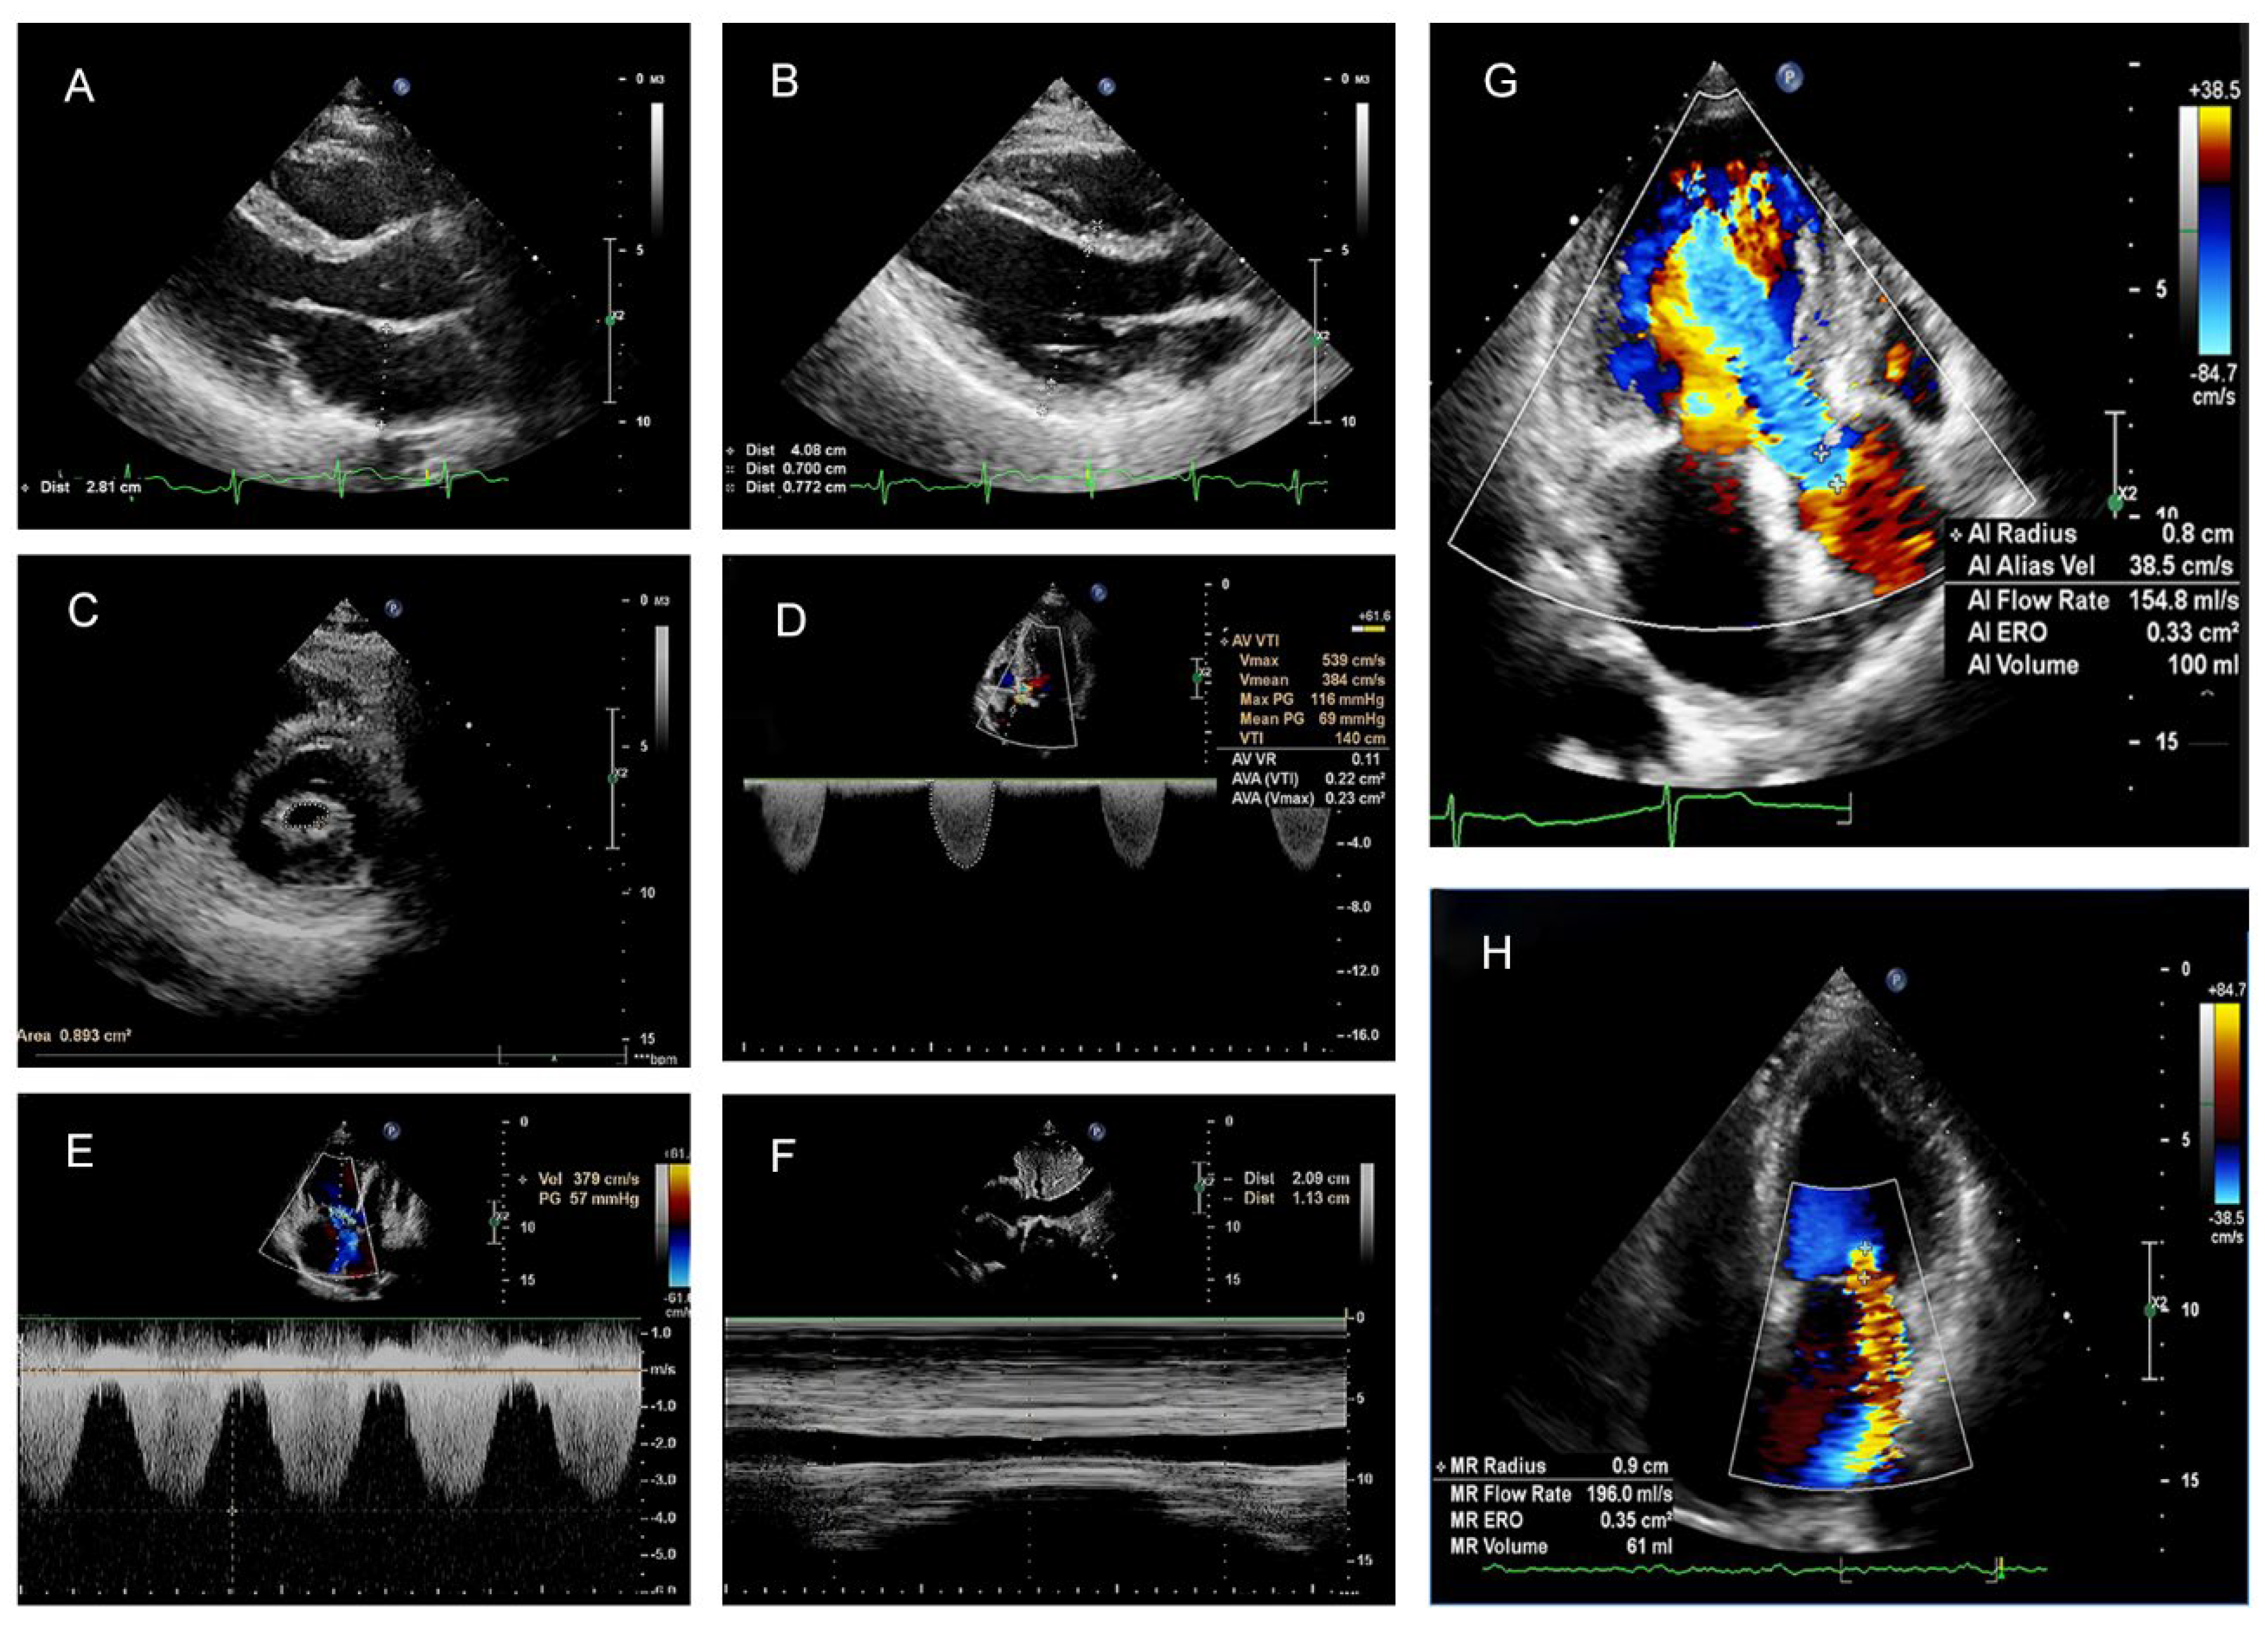

2.2. Echocardiographic Parameters

3.2. Transthoracic Doppler Echocardiography Index (TTEI)